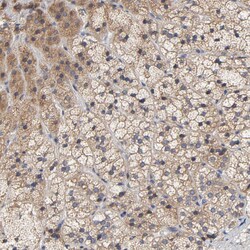

Invitrogen™ CCDC134 Polyclonal Antibody

The coiled-coil domain is a common protein motif that is often involved in protein oligomerization and is found in proteins such as transcription factors and intermediate filaments. One such protein is CCDC134, a recently identified secretory protein that has been found to inhibit the transcriptional activity of the Elk1 protein. Overexpression CCDC134 also inhibited the phosphorylation of Erk and JNK/SAPK but not p38 MAPK, while specific siRNA against CCDC134 activated Elk1 transcriptional activity and the phosphorylation of Erk and JNK/SAPK, suggesting a potential inhibiting role of CCDC134 in MAPK-mediated Elk1 transcription. CCDC134 is widely expressing in normal adult tissues, tumors, and cell lines.

| Applications | Immunohistochemistry (Paraffin), Western Blot |